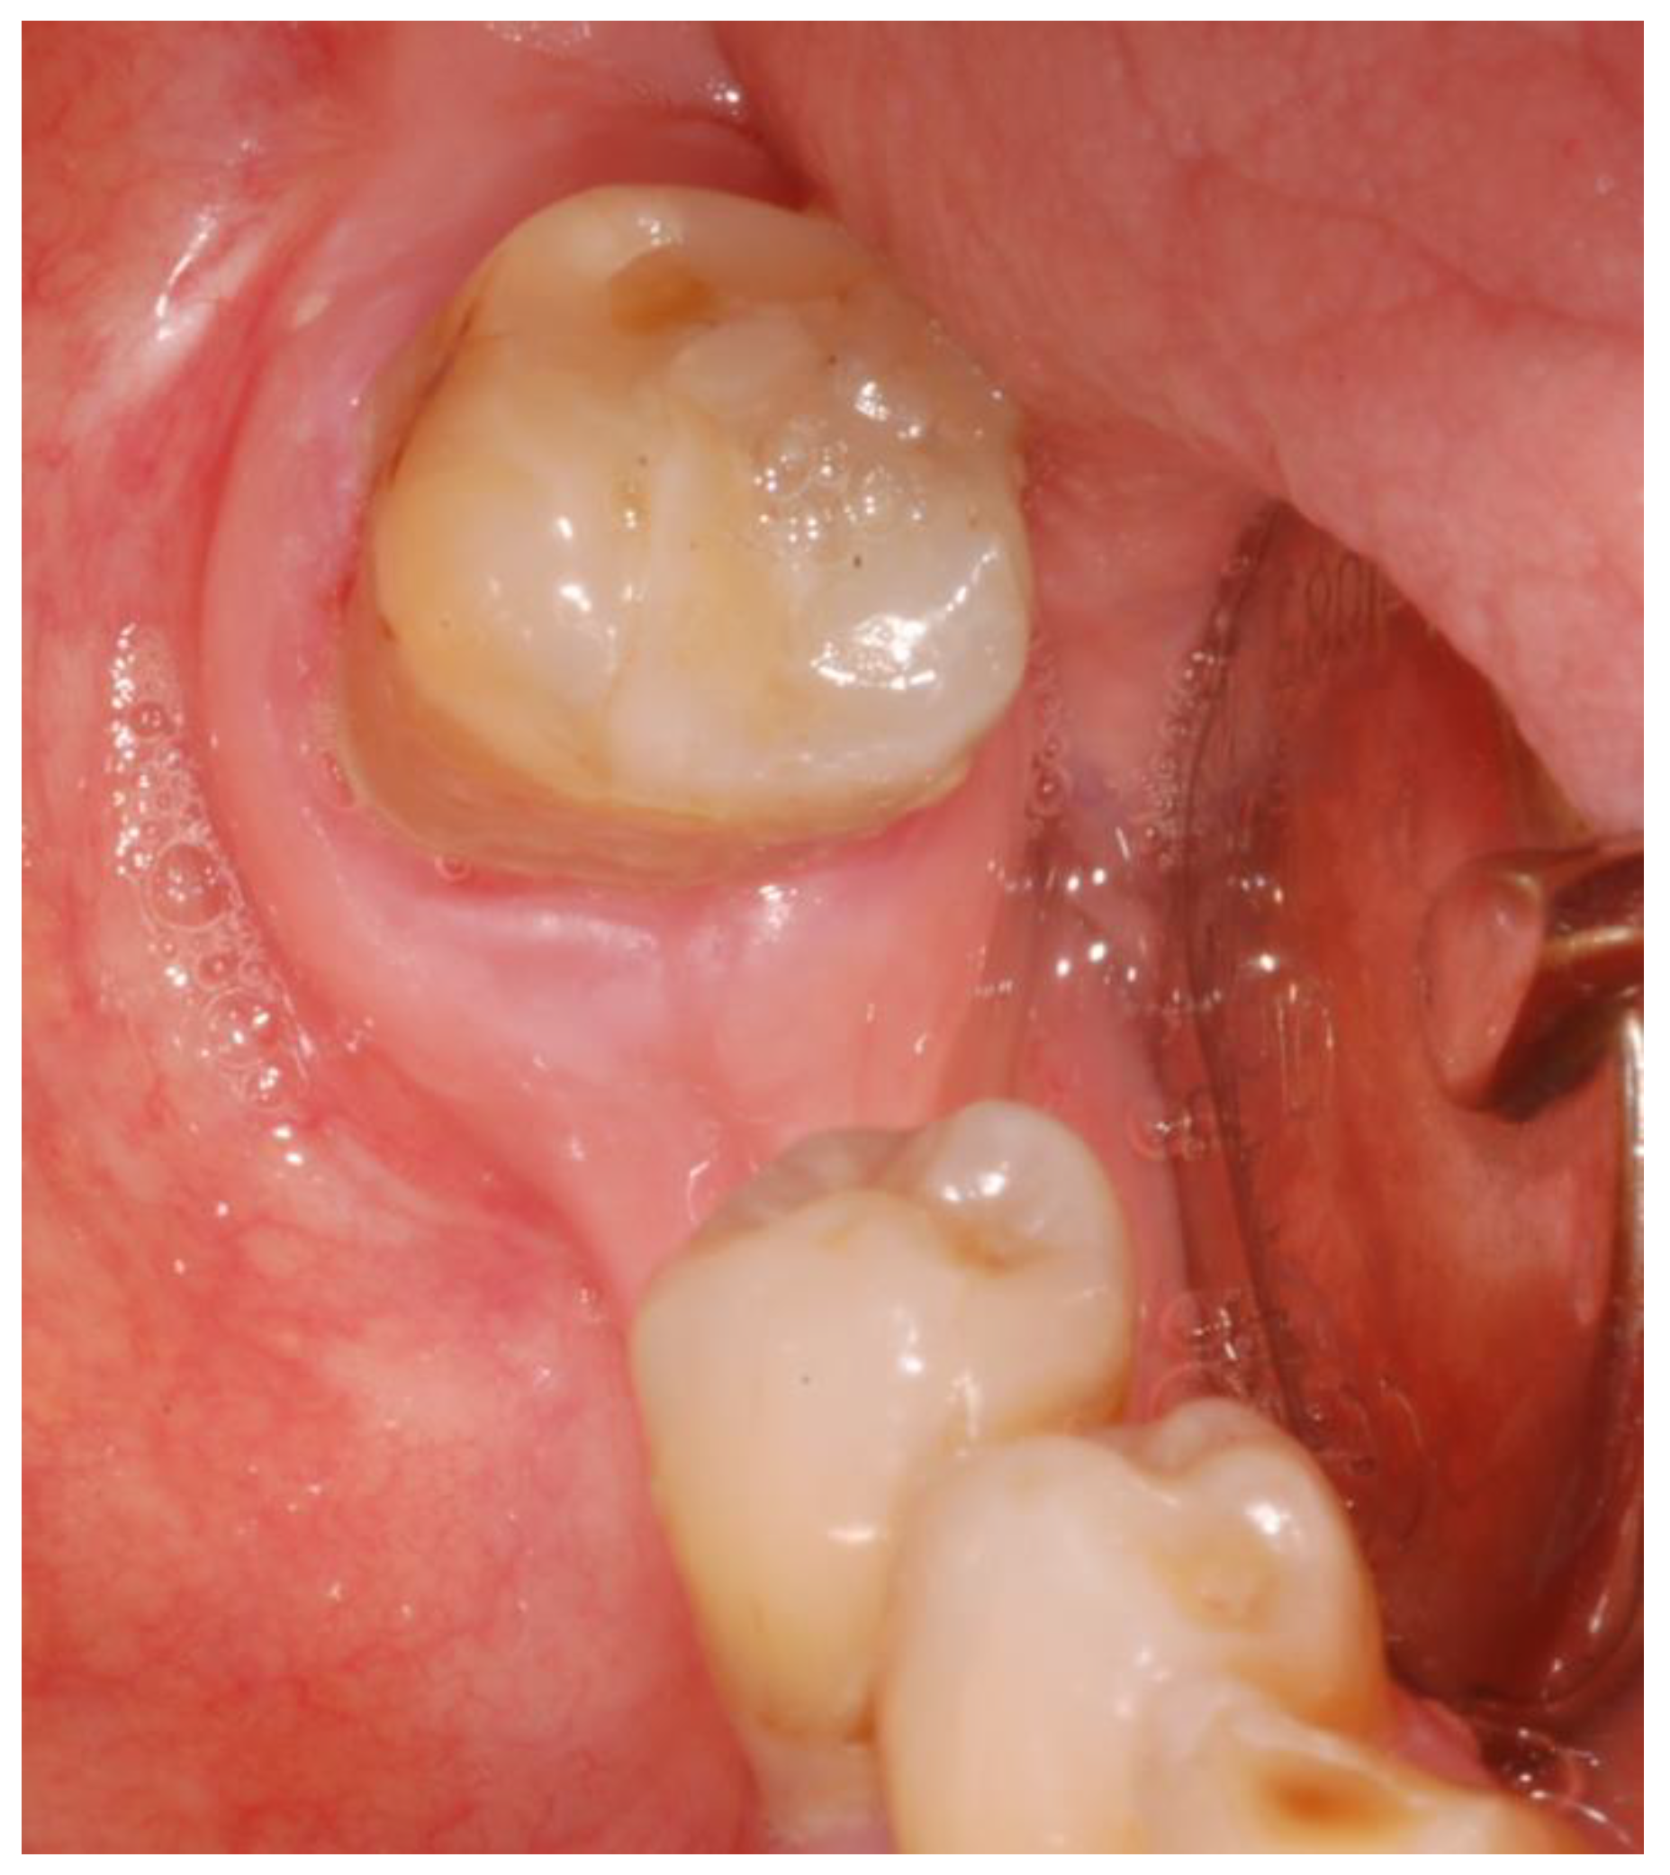

2.1. Case Presentation

- Surgery timing. The surgeon can follow in real time the ultrasonic tip position onto the system screen displaying the CBCT images and safely identify and remove the necrotic bone surrounding the inferior alveolar nerve on the right side.